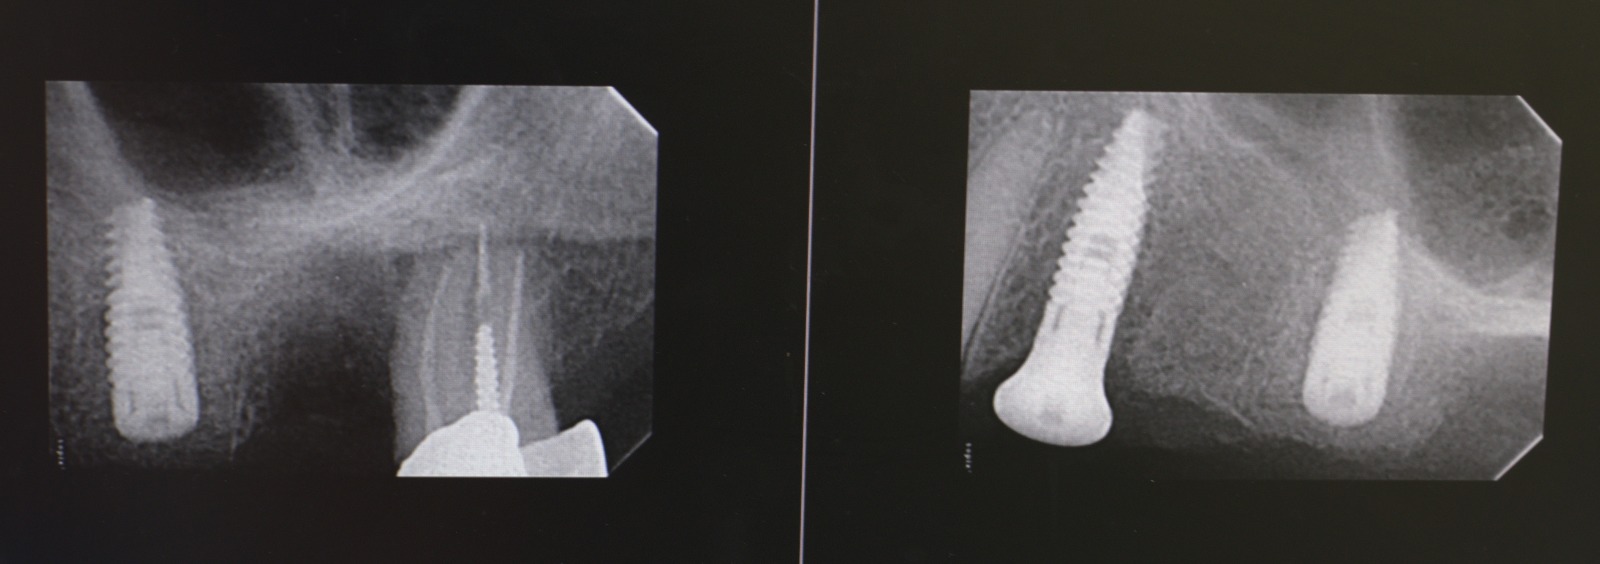

Multiple post-extraction implantation in multiple techniques - bone condensing, septum of molar placement, guided bone regeneration